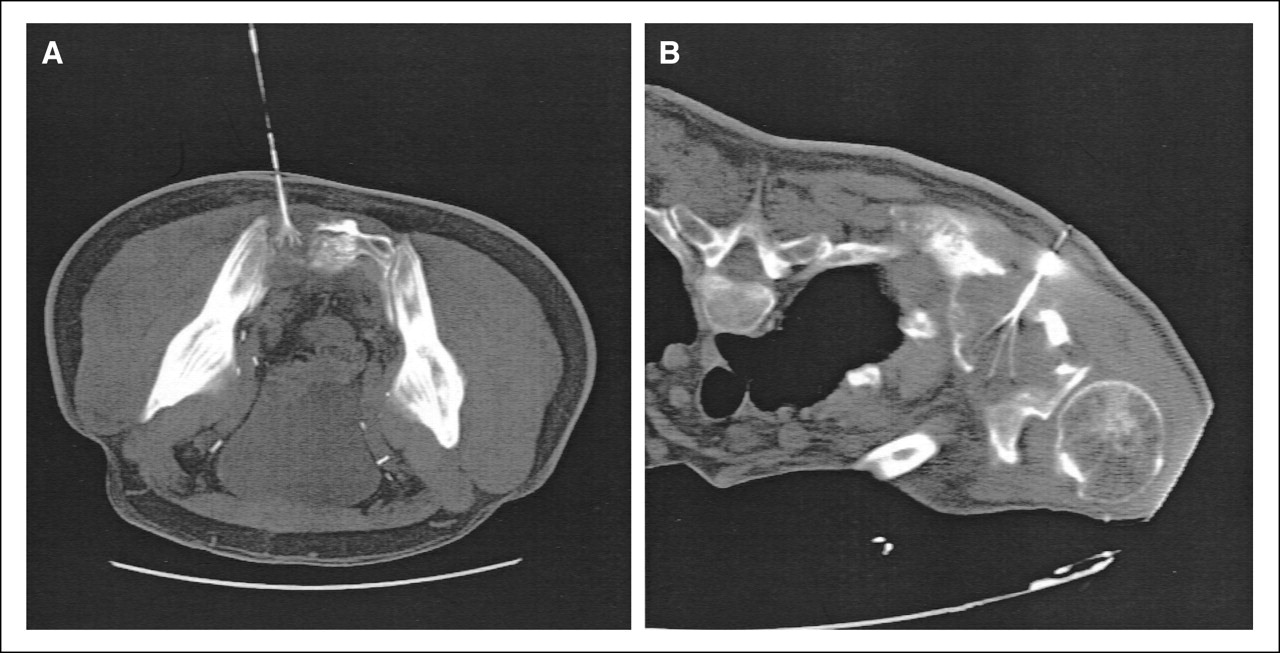

Bệnh nhân nữ, 58 tuổi, tiền sử ung thư ống vòi trứng> 2 năm.

A. Khối di căn phần mềm vùng bẹn trái, kèm huyết khối tĩnh mạch đùi (mũi tên đen), khối ngấm thuốc mạnh sau tiêm (mũi tên trắng).

B. Khối phần mềm sau khi đốt sóng cao tần không còn ngấm thuốc sau tiêm.